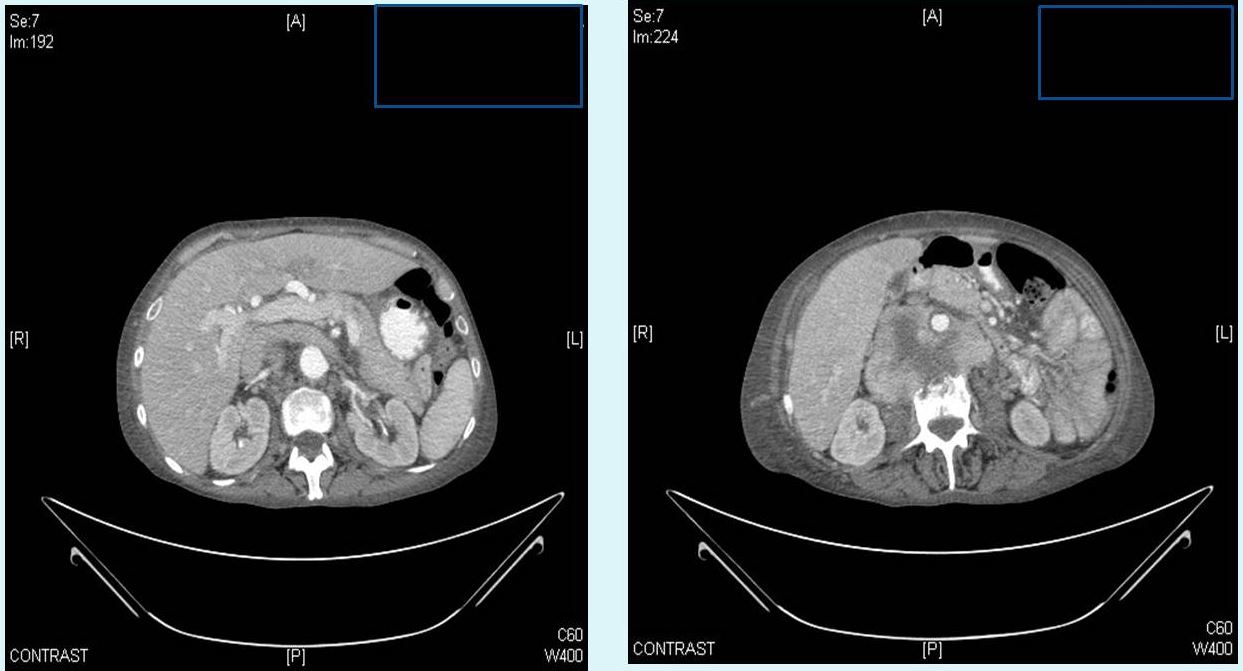

En la radiografía de tórax se apreciaba derrame pleural derecho y en el TAC de abdomen una masa retroperitoneal heterogénea que englobaba, comprimía y desplazaba ventralmente la vena cava inferior y la aorta […], con afectación del cuerpo vertebral de L3.

Todos estos hallazgos fueron sugerentes en primera instancia de sarcoma peritoneal, confirmados posteriormente tras su ingreso en planta.